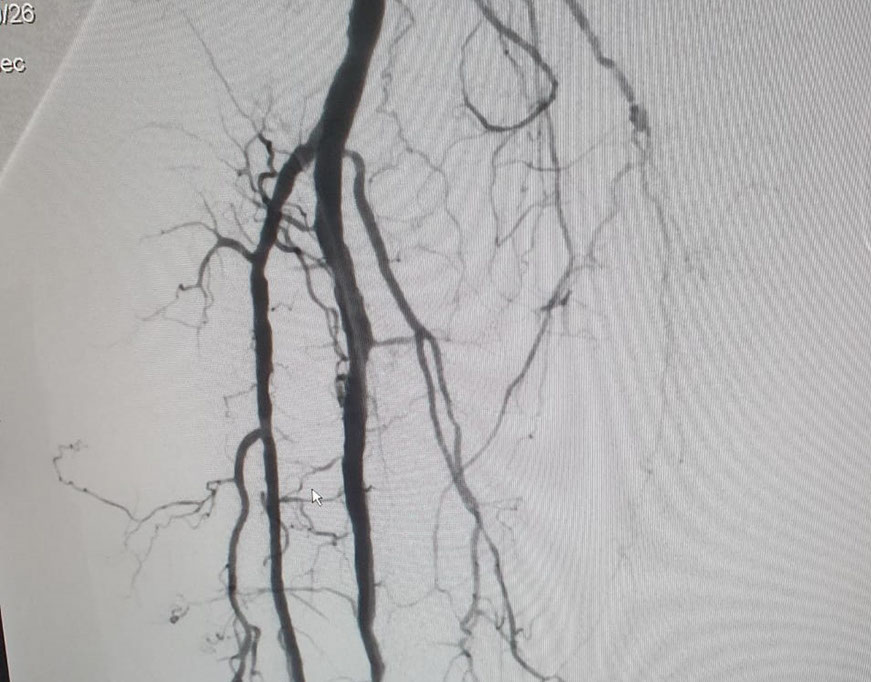

Las imágenes siguientes son previas al procedimiento y posterior se ve ambas arterias tíbiales permeables, y circulación en el pie